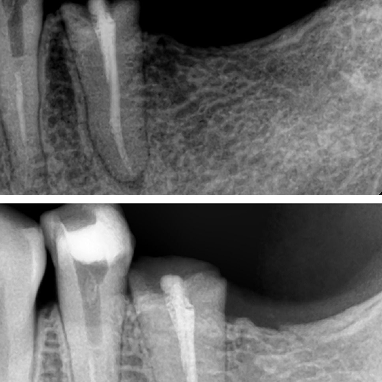

Nyeri akibat gigi berlubang parah dapat segera teratasi, bahkan sejak kunjungan pertama.

Dengan penanganan dokter gigi berpengalaman di Dharmawangsa Dental Studio, perawatan saluran akar dilakukan dengan teknologi modern sehingga nyeri hilang lebih cepat dan pasien merasa nyaman.